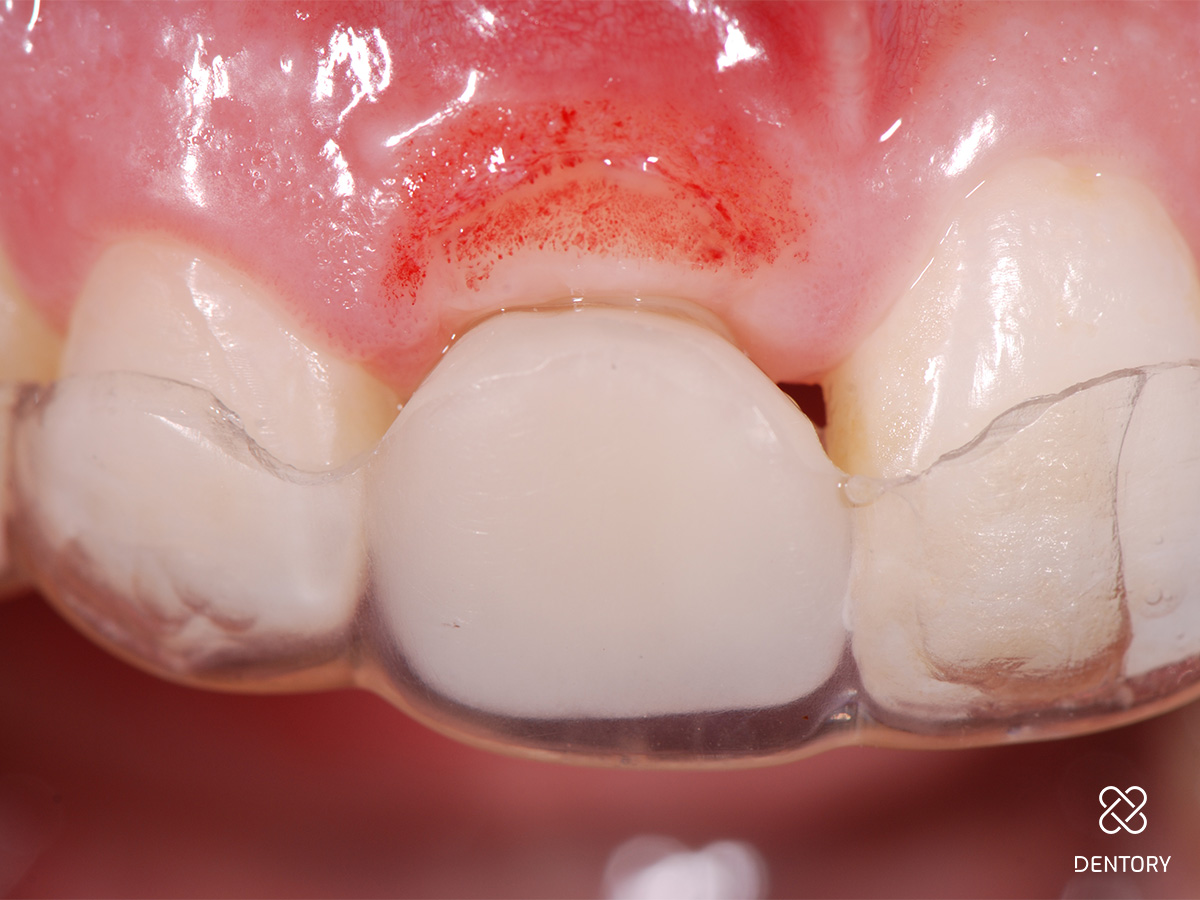

Abbildung 1

Ausgangssituation: Nicht erhaltungswürdiger Zahn 11 aufgrund einer externen Resorption.